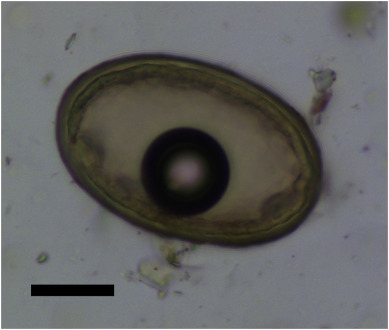

They found that eggs from two species of parasitic worm (helminths) were present: whipworm (Trichuris trichiura), and roundworm (Ascaris lumbricoides). Whipworm was present from the Neolithic, and roundworm from the Bronze Age.

Abstract Little is known about infectious disease and parasites in the prehistoric inhabitants of the islands of the Aegean, in contrast to later time periods. It is only with the development of Greek medical texts in the 5th and 4th centuries BC we start to find evidence for the diseases that affected the population of region. Foremost amongst these authors was the medical practitioner Hippocrates, who lived on the island of Kos. The descriptions of the many diseases he and his students encountered were recorded in their medical texts in the 4th and 3rd centuries BC, known as the Hippocratic Corpus. These important texts provided the core philosophy underpinning medical theories in Europe and the Arab world for the following 2,000 years. Past research to determine which species of intestinal parasitic worms were described in the Hippocratic Corpus has suggested they indicate roundworm, pinworm and Taenia tapeworm. However, until now, there has been no archaeological evidence for which species of helminths were present in ancient Greece. In this study, we analysed soil sediment adherent to the sacrum and iliac bones of the pelvis of 25 burials dating from the Neolithic to Byzantine period on the Greek island of Kea, not far from Kos. Four individuals (16%) were positive for the eggs of intestinal helminths, dating from the Neolithic (4th millennium BC), Late Bronze Age, and the Roman Period. The species identified were whipworm (Trichuris trichiura) and roundworm (Ascaris lumbricoides). We consider reasons as to why fewer species of parasite appear to have been present on Kea than was the case for northern Europe at the same time period. This study of ancient parasites shows how we can combine archaeology with history of medicine to better understand the discoveries of key early scientists and medical practitioners.